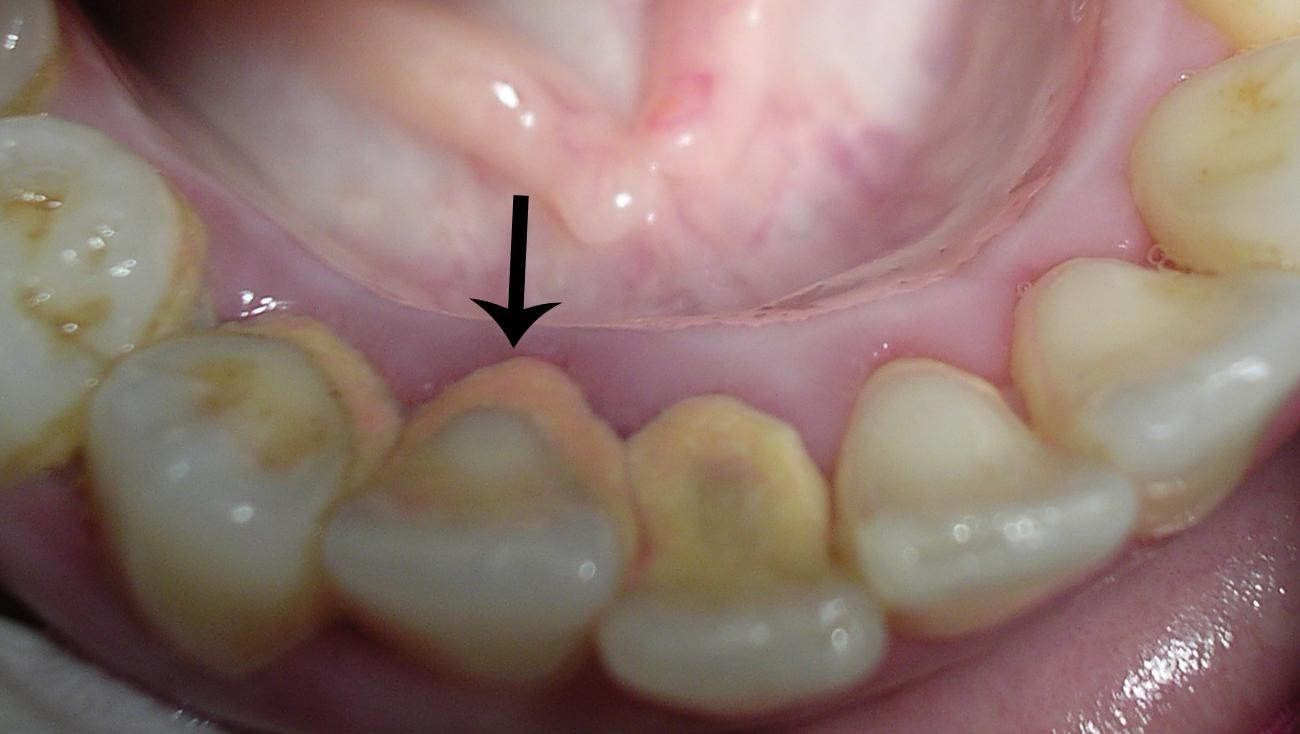

Выраженный пародонтит и гингивит. Дёсны синюшные, массовые скопления зубного налёта и камня.

По мере развития пародонтита мы можем видеть убыль костной ткани и обнажающиеся корни зубов. Вместо нормальных десневых сосочков появляются некрасивые чёрные пустые треугольники.